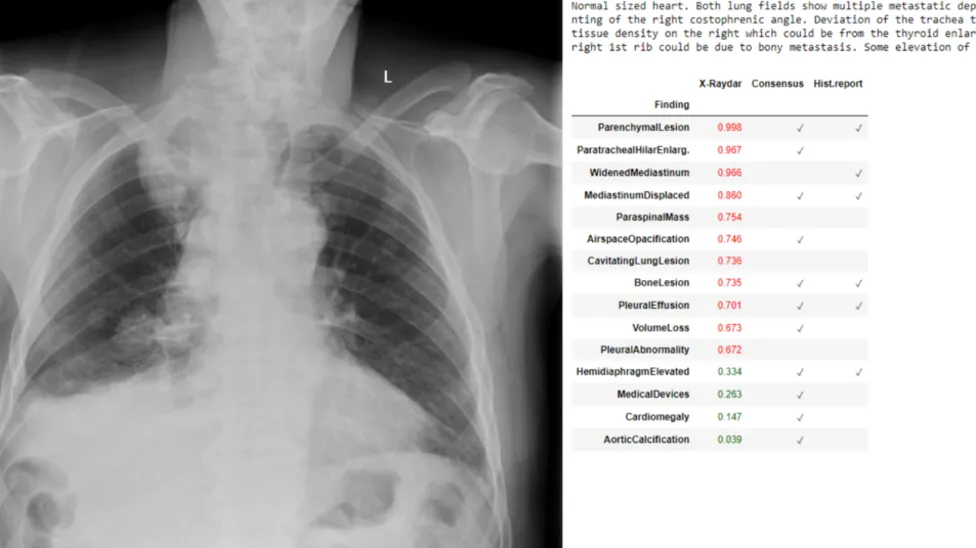

📰 인공지능이 진단하는 흉부 X-선, X-raydar 프로젝트

📰요약 : X-raydar 프로젝트는 인공지능을 이용해 흉부 X-선 이미지를 분석, 진단하는 기술을 개발 중입니다. 흉부 X-선은 심폐 이상의 진단에 있어서 효과적이고 비용이 낮고 복사선 부담이 적으며 진단 절차가 간편하기 때문에 세계 의료 이미징의 40%를 차지하고 있습니다.

🗣논평: X-raydar의 등장은 의료 진단의 패러다임을 변화시키고 있습니다. 이 기술은 특히 자원이 부족한 지역에서의 의료 접근성 향상에 중요한 역할을 할 것으로 기대됩니다. 인공지능의 정확성과 속도는 전문가 부족 문제를 완화하고, COVID-19 같은 대유행 상황에서 신속한 대응에 기여할 수 있습니다. 그러나, 이러한 기술의 윤리적, 법적 측면에 대한 논의도 필요합니다. X-raydar 프로젝트는 의료계에 혁신적인 변화를 가져오면서도 새로운 도전과 기회를 제시합니다.